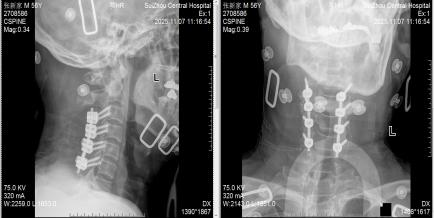

圖3:術(shù)后X線見內(nèi)固定位置良好